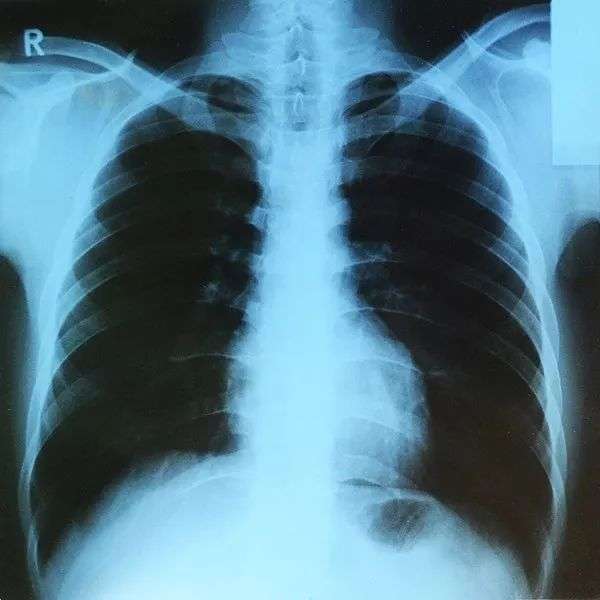

X线检查很常用,如体检拍胸片或摔倒后排除骨折时都会用到。其影响取决于胎龄和射线剂量。

单次X线检查一般不会伤害胎儿,但多次高剂量的检查可能导致胚胎死亡、先天畸形、生长受限及智力缺陷等。

人体肺部的X射线 | Wikimedia Commons